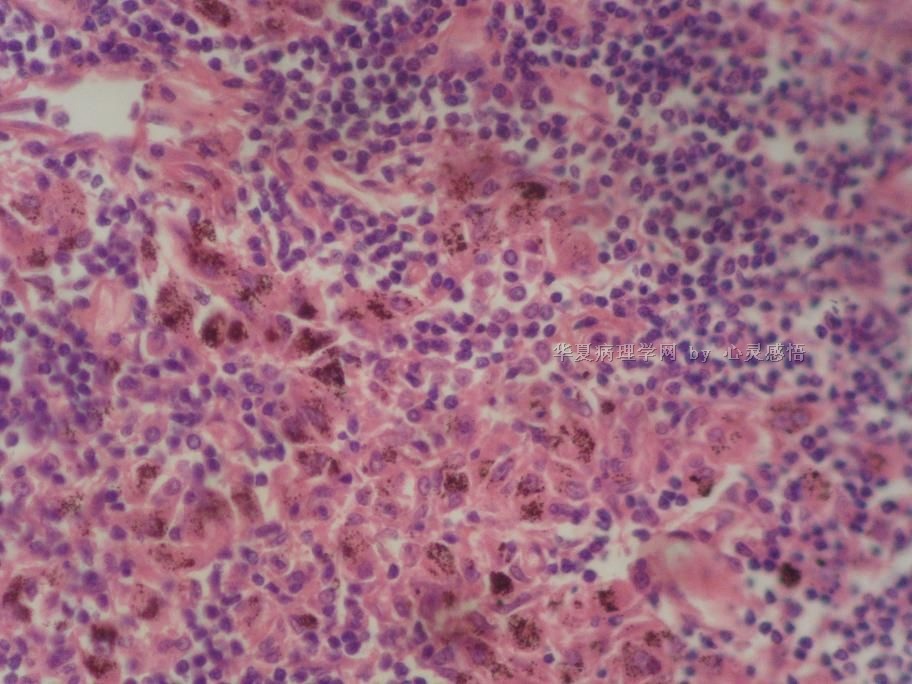

• 食道癌,淋巴结有没有转移,谢谢。图3

图3

1-6图是鳞癌。7-22图片无癌。

淋巴结没有转移

本帖最后由 于 2010-11-17 20:19:00 编辑  图14,19有转移

没有转移。

没有转移,食道旁的淋巴结和肺旁的淋巴结相似,含有吞噬细胞。